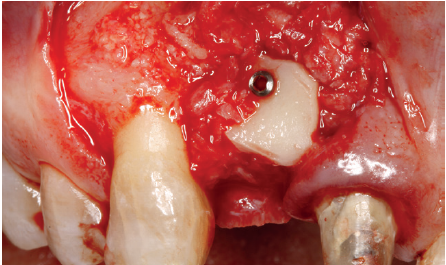

Cuatro meses después, se realiza un nuevo Cone-Beam dental para poder cuantificar la ganancia obtenida en anchura con el procedimiento regenerativo. Se observa en el corte seccional como se ha logrado una anchura de cresta de más de 7 mm y una regeneración completa del reborde alveolar, lo que permite la inserción de un nuevo implante dental en la posición adecuada (Figura 10). En la reentrada quirúrgica se constata la información del Cone-Beam con una integración total del material de injerto, tal como se muestra en las imágenes clínicas en el momento de la elevación del colgajo para la inserción del implante (Figuras 11 y 12). Se procede a la retirada del microtornillo y la colocación del implante, que se realiza mediante la compresión vestibular del injerto para ganar de esta manera aún más contorno en esta área (Figura 13). El implante se deja en una fase quirúrgica, con un pilar de cicatrización bajo que permita una localización posterior del mismo sin una cirugía agresiva del tejido blando para cuando se inicie la confección de la prótesis. El provisional sigue siendo una pieza en extensión desde el diente 1.1.